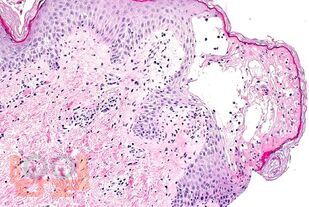

В учебном пособии представлены современные сведения об этиологии, эпидемиологии, основных аспектах патогенеза, клинических проявлениях, диагностике, дифференциальной диагностике, лечении и профилактике энтеровирусных неполиомиелитных инфекций.